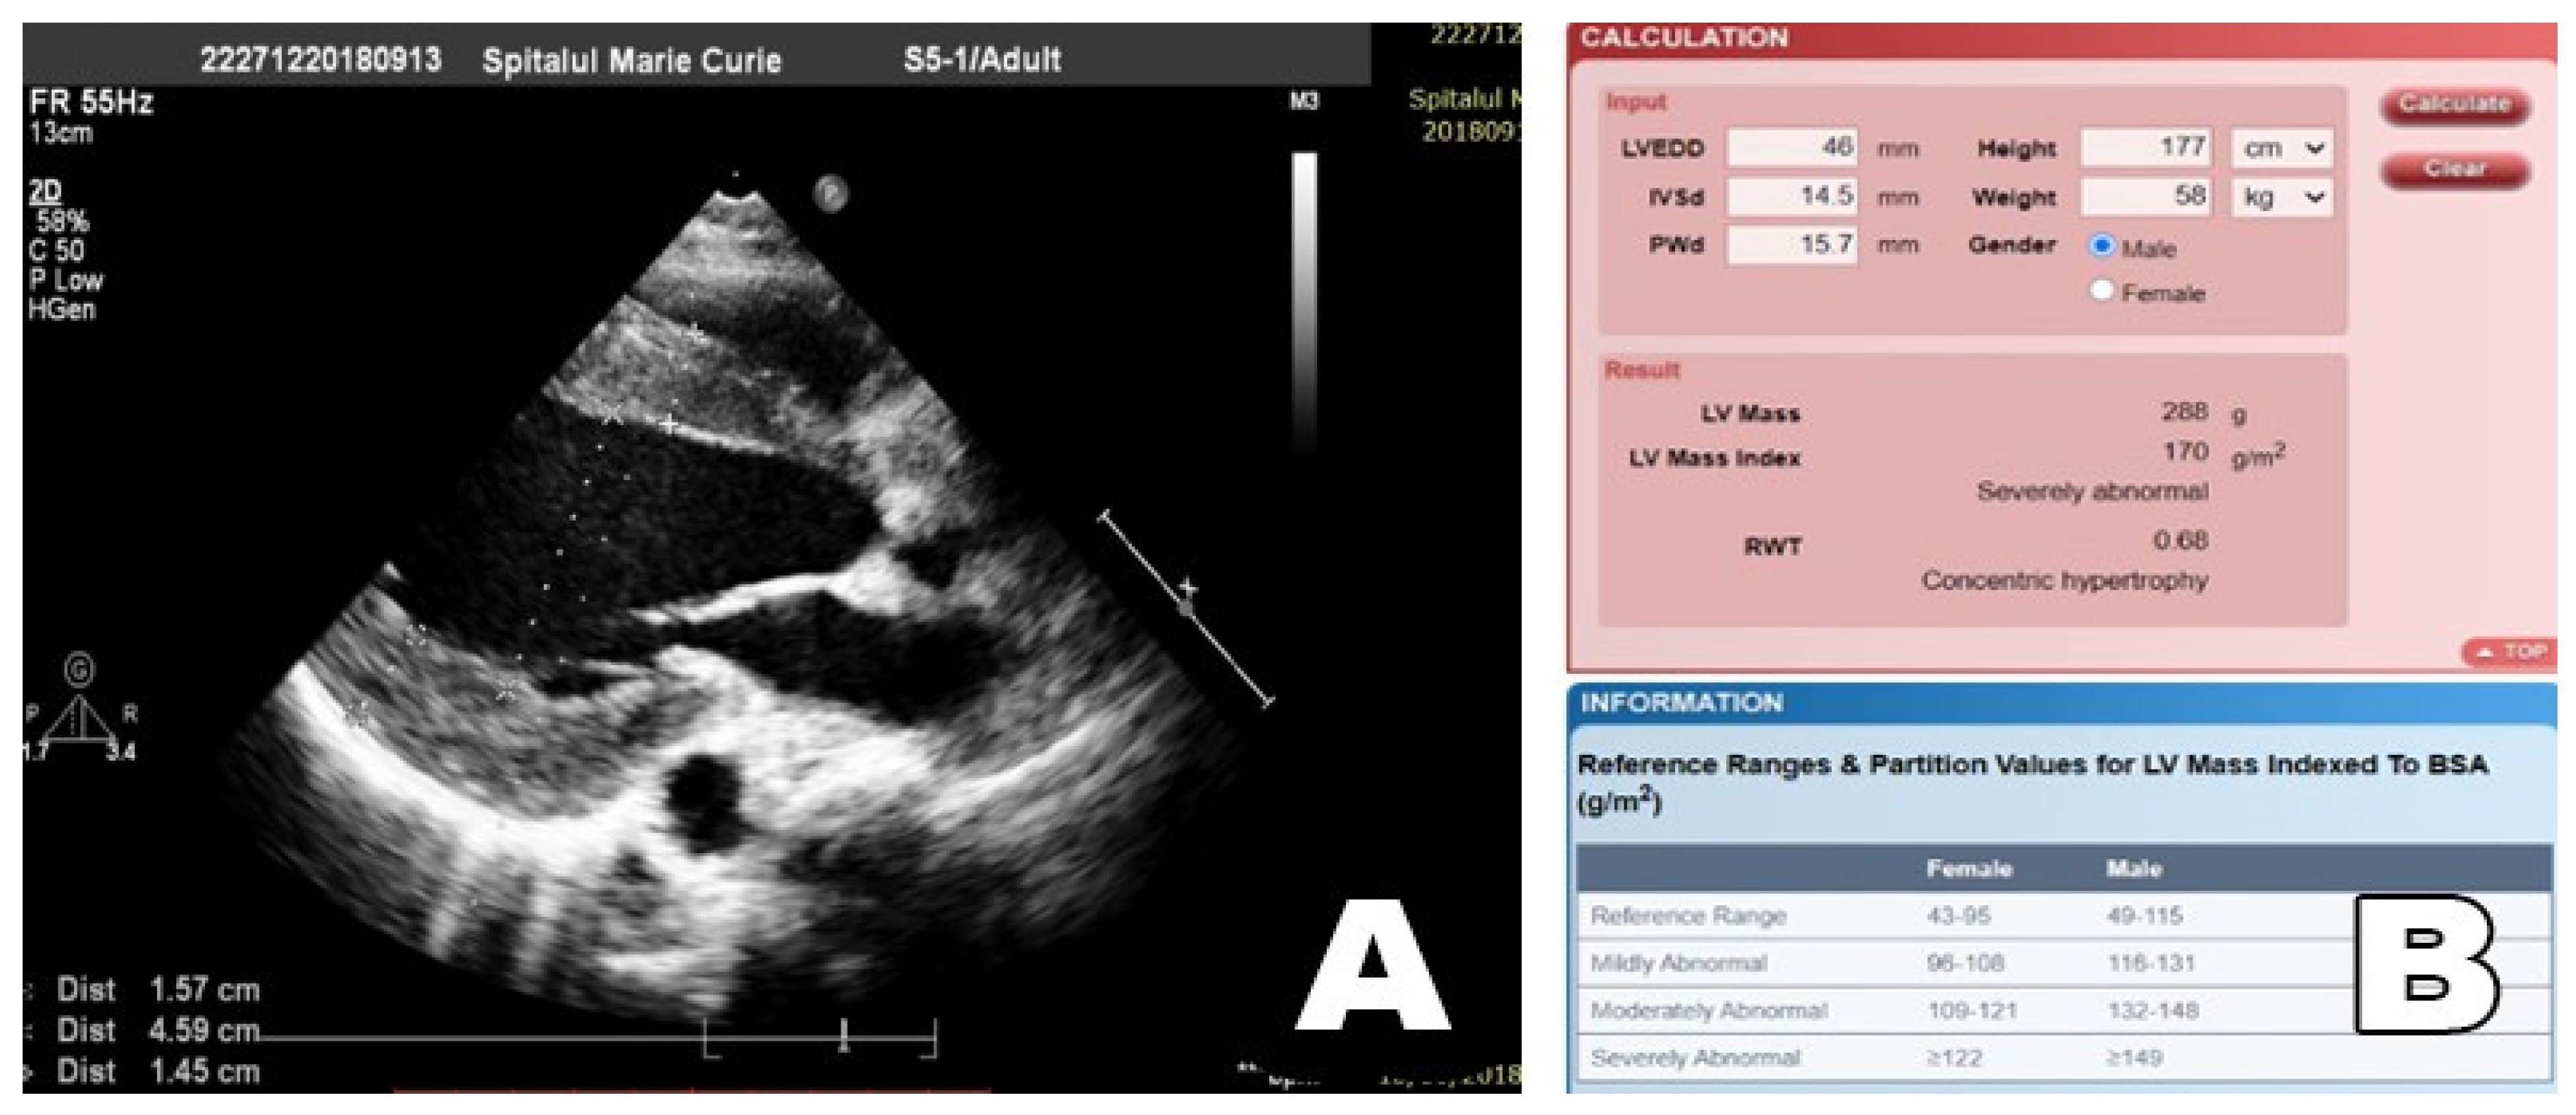

| IVS (mm) interventricular sept | 8.5 ± 1.202 (7.5–10) | 8.667 ± 1.291 (8–10) | 11.92 ± 1.9 (10.5–13.5) | 10.25 ± 1.75 (9–10.88) |

| PW (mm) Posterior wall | 7.7 ± 0.856 (7.5–8.25) | 7.583 ± 0.97 (7.125–8.250) | 11.39 ± 2.4 (9.85–12.75) | 9.438 ± 1.613 (8.625–9.875) |

| Left ventricle (LV) g/m2 | 87.6 ± 12.53 (76.75–95.75) | 87.67 ± 14.15 (75.25–99) | 150 ± 56.4 (111.5–166) | 128.1 ± 44.92 (97.25–133.5) |

| LV mass index g/m2 | 87.6 ± 12.53 (76.75–95.75) | 87.67 ± 14.15 (75.25–99) | 150 ± 56.41 (111.5–166) | 128 ± 44.92 (97.25–133.5) |